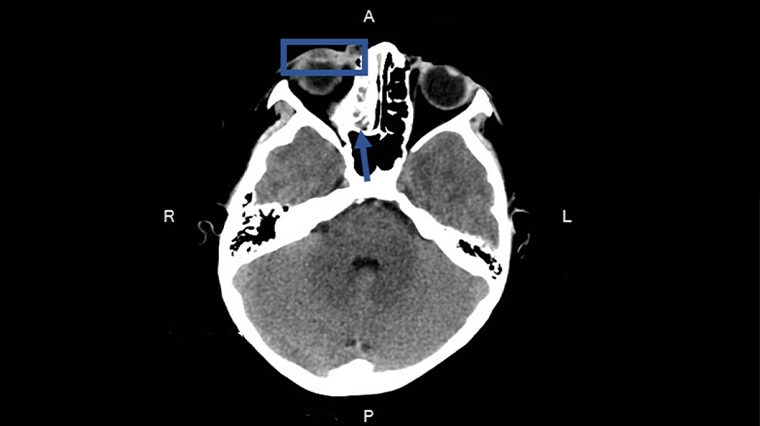

收治這名男童的新竹臺大分院小兒部醫師許瑋芸說,在診察時便發現男童右眼下眼瞼紅腫並壓痛,範圍超過下眼瞼,進一步安排抽血檢查顯示白血球數值及發炎指數顯著上升。醫療團隊當即進行電腦斷層檢查並安排住院,經評估與檢查後,確診為「隔膜前(眼眶周圍)蜂窩性組織炎」,予以男童靜脈抗生素治療,病況才逐漸改善,也改以口服抗生素持續治療。目前男童已順利出院返家休養,在後續門診追蹤時也已完全康復。

許瑋芸醫師解釋,眼球周圍的感染可分為「隔膜前(眼眶周圍)蜂窩性組織炎」及「眼窩蜂窩性組織炎」,兩者皆可能因鼻竇炎惡化或眼眶周圍皮膚感染導致細菌擴散至眼球周圍構造。